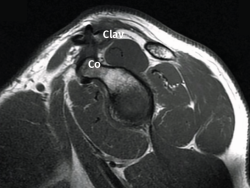

Figura 4. Los túneles óseos taladrados en el extremo distal de la clavícula (Clav) y el cuello de la coracoides (Co) se conectan entre sí mediante un hilo Vicryl® que hace de pasador final del dispositivo elegido. Hombro derecho con la óptica en un abordaje anterolateral.

La técnica artroscópica empleada fue la denominada de cerclaje de suspensión cortical coracoclavicular(2). Por encontrarnos más habituados, empleamos la posición de decúbito lateral y los portales de artroscopia posterior, anterolateral y 2 portales anteriores realizados para abordar el espacio subcoracoideo bajo visión directa, según la técnica descrita(5,6,7). En los 6 primeros casos empleamos el dispositivo AC TightRope® (Arthrex, Inc., Naples, Florida). A pesar de su analogía, pero motivado por el cambio de diseño realizado en dicho dispositivo y por el menor orificio requerido, en los 16 restantes casos hemos utilizado el dispositivo AC EndoButton TwinBrigde® (Smith & Nephew, London, England). En los casos con lesiones acompañantes, se emplearon los dispositivos OsteoRaptor 2,3® (Smith & Nephew, London, England) para la reconstrucción de las lesiones de tipo SLAP y el dispositivo TwinFix PK 5,5® (Smith & Nephew, London, England) para el tratamiento de las lesiones de los tendones del manguito rotador. En los últimos 6 casos hemos desestimado el empleo de las guías diseñadas para la implantación de estos dispositivos. Encontramos que su empleo es engorroso, dificulta la selección de los puntos de realización de los túneles óseos y prolonga el tiempo quirúrgico. Optamos por la inserción de las agujas-guía en el extremo clavicular al comienzo de la intervención (Figura 2). En este momento los relieves óseos son fácilmente apreciables. La selección del punto en el cuello de la coracoides se realiza de forma percutánea bajo visión directa (Figura 3). Tras realizar los túneles óseos por taladrado sobre las agujas-guía en la forma habitual, estos se conectan mediante un hilo Vicryl® n.º 2 (Ethicon Endo-Surgery Inc., Cincinnati, Ohio, United States) que hace de pasador final del dispositivo elegido (Figura 4). Si es necesario, se completa la reparación de la fascia trapeciodeltoidea y/o de la cápsula acromioclavicular superior a través del miniabordaje superior asociado.